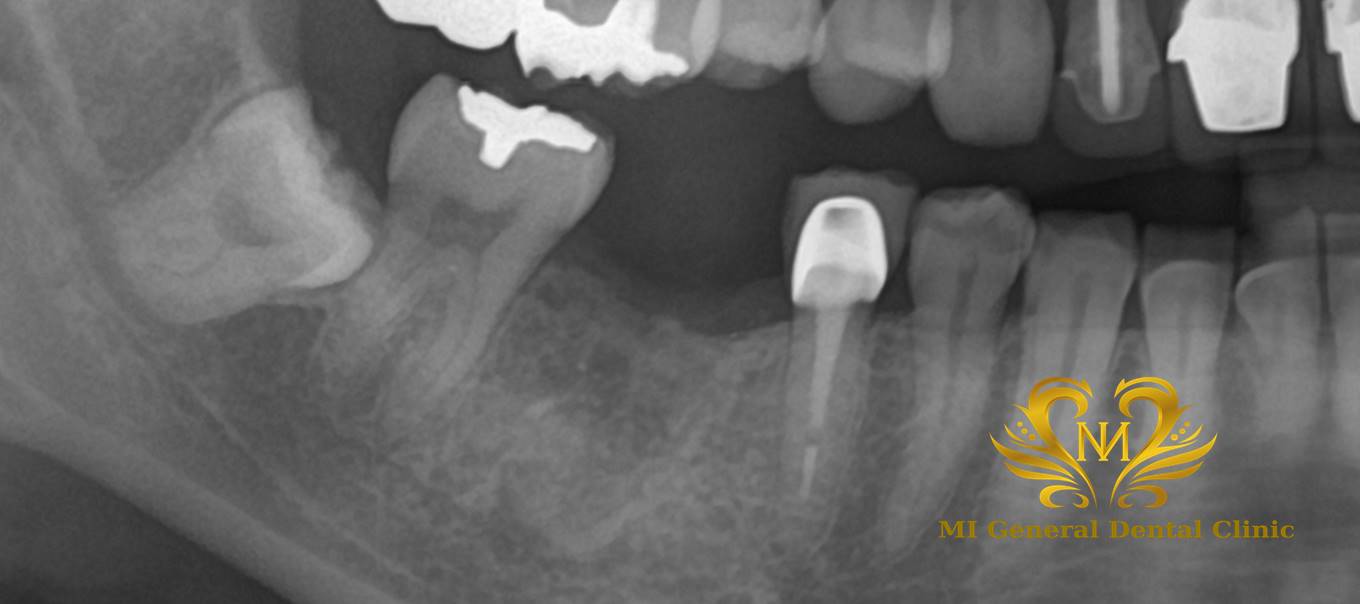

治療前

右下の奥歯の歯がありません。

右下の奥歯が1本ありません。

歯を抜歯して噛みにくい。

治療内容

欠損補綴の説明(インプラント、ブリッジ、入れ歯)をし、インプラント治療を希望された為、右下の奥歯にインプラント体埋入後に、骨とインプラント体の定着を待ちセラミックスを被せました。